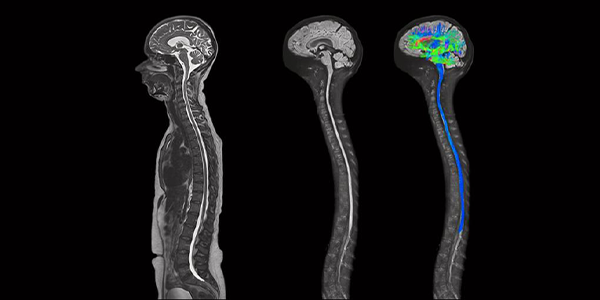

Difüzyon MR, beyindeki su moleküllerinin hareketini ölçerek beyin dokularının mikroyapısı hakkında detaylı bilgi sağlayan bir MR tekniğidir. Bu yöntem, özellikle beyindeki sinir liflerinin yönünü ve bütünlüğünü görüntülemek için kullanılır. Difüzyon MR, inme, travmatik beyin hasarı, multipl skleroz (MS) ve beyin tümörleri gibi nörolojik hastalıkların teşhisinde ve takibinde önemli bir rol oynar.

Difüzyon MR, su moleküllerinin rastgele hareketlerini (difüzyon) ölçerek çalışır. Normal beyin dokusunda su molekülleri serbestçe hareket eder. Ancak bir lezyon (örneğin, bir tümör veya inme) varlığında, su moleküllerinin hareketi kısıtlanır. Difüzyon MR, bu kısıtlamayı algılayarak lezyonları tespit edebilir.

• Difüzyon Ağırlıklı Görüntüleme (DWI): DWI, su moleküllerinin hareketini ölçerek beyin dokusundaki anormallikleri tespit etmek için kullanılan bir difüzyon MR tekniğidir. İnme, tümörler ve enfeksiyonlar gibi durumlarda su difüzyonu kısıtlanır ve bu bölgeler DWI görüntülerinde parlak olarak görünür.

• Difüzyon Tensör Görüntüleme (DTI): DTI, su moleküllerinin hareket yönünü ve derecesini ölçerek beyindeki sinir lif yollarının haritasını çıkarır. Bu yöntem, beyin bağlantılarını değerlendirmek ve travmatik beyin hasarı, inme ve diğer nörolojik hastalıkların teşhisinde kullanılabilir. Ayrıca, beyin cerrahisi öncesinde planlama yapmak ve kritik beyin bölgelerinden kaçınmak için de kullanılabilir.

• Traktografi: DTI verilerini kullanarak beyindeki sinir lif yollarının üç boyutlu görüntülerini oluşturur. Bu yöntem, beyin bağlantılarını daha iyi anlamak ve cerrahi planlama için kullanılabilir.